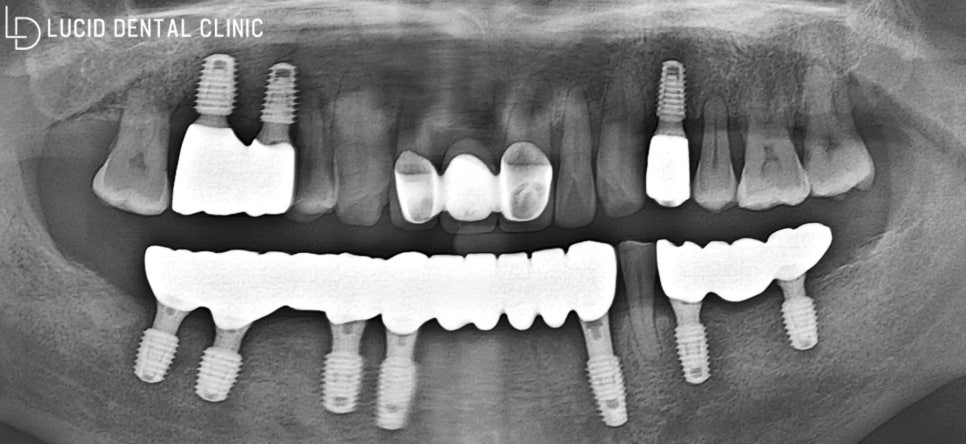

그럼, 임플란트 최종 종료 후는

어떤 모습일지, 보러 갈까요?

- 최종 종료

환자의 나이 및 회복 능력을 고려하여

조금씩 나눠서 치료를 진행했었는데요

그 결과, 한층 더 나은 방향으로

결과가 나올 수 있었던 것 같아

저도, 환자도 크게 만족스러웠던

치료 중 하나였다고 생각합니다 :)

실제로 초진 구내 모습과 비교하면

심미는 물론, 기능까지 온전하게

되찾은 모습을 볼 수 있습니다.